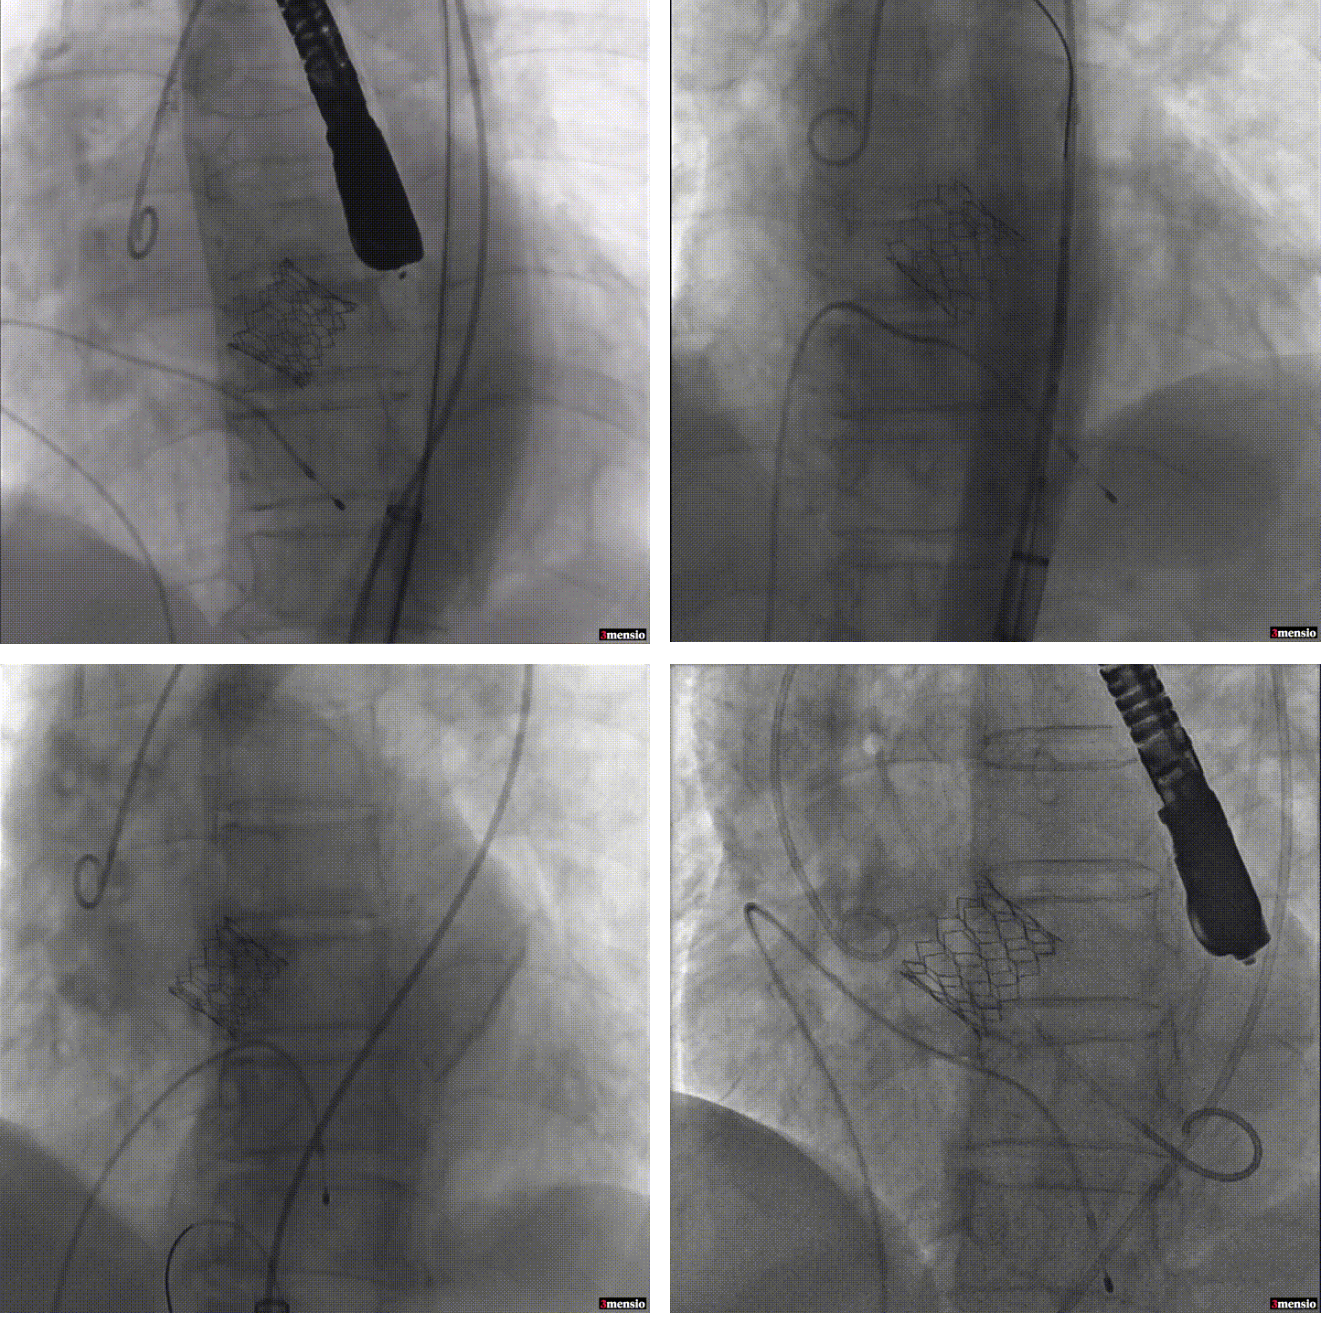

近日温州医科大学附属第一医院心脏外科连续完成了7例佰仁球扩TAVI瓣膜手术,术中心超及随访复查结果都非常满意,没有一例并发症,完美解决了患者瓣膜狭窄的问题。

如下图所示,取得了极其满意的效果。

瓣膜释放 瓣膜释放后造影